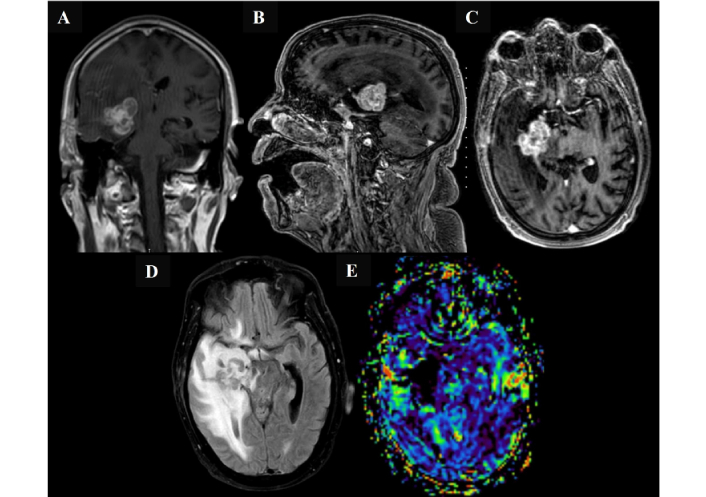

Following review by the multidisciplinary team (MDT) and given an unchanged lesion size on serial MRI (Figure 4), a third biopsy was performed via right temporal craniotomy and open biopsy on 12 March 2025. The lesion appeared intra-axial, firm, and greyish intraoperatively; debulking was limited to tissue sampling following diagnostic confirmation.

Magnetic resonance imaging findings following initial chemotherapy in March 2025, before the open biopsy surgery. Magnetic resonance imaging of the brain demonstrates a deep seated right medial temporal lobe intra-axial mass with interval progression in size, now involving the right gangliocapsular region. The lesion shows predominantly low signal intensity on both T2- and T1-weighted images, with corresponding low apparent diffusion coefficient values and intense heterogeneous post-contrast enhancement. The lesion measures 3.4 cm × 2.9 cm × 3.6 cm (anteroposterior × transverse × craniocaudal) (A, B, and C). Marked progression of adjacent vasogenic edema and regional mass effect are noted, including effacement of the right lateral and third ventricles with right temporal horn dilatation (D). A midline shift of 3.6 mm toward the left is also observed. No other significant interval changes were detected. There is no evidence of elevated relative cerebral blood volume on perfusion imaging (E).